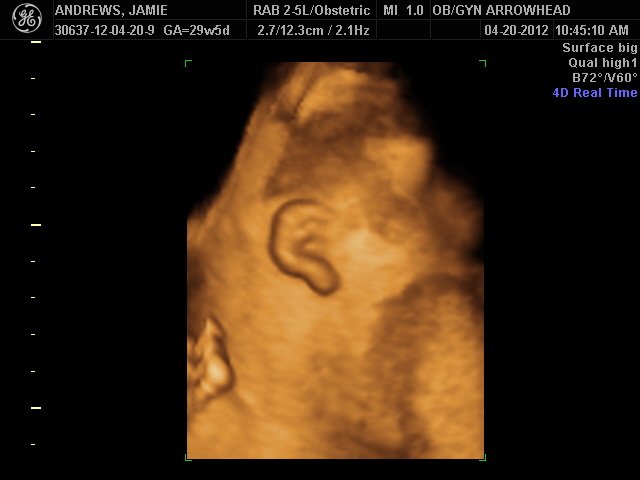

We offer complimentary 3D/4D Ultrasounds to all our OB patients around 30 weeks! The following photos are some examples of our work, shown with permission from our patients.